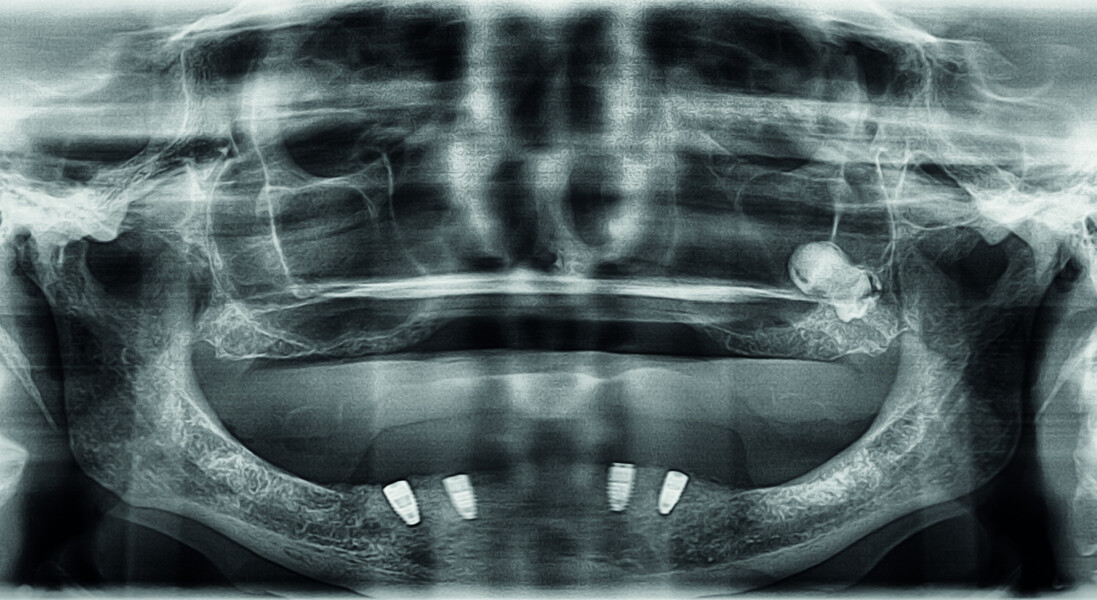

Digitising your implant practice